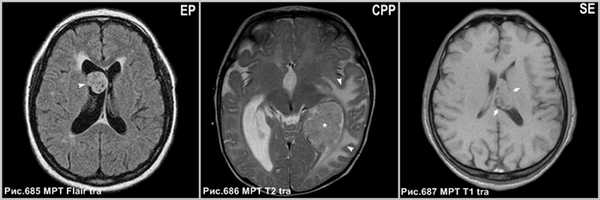

Эпендимома чаще встречается в детском возрасте, в основном, поражает IV желудочек и распространяется через желудочковые отверстия (рис.685).

Хориоидпапиллома (рис.686) встречается, главным образом, у детей; типично интенсивное контрастирование опухоли и внутриопухолевого питающего сосуда.

Субэпендимома обычно встречаются в IV желудочке, поражает людей старшего возраста (рис.687).

![central_neurocytoma_4]()

Эпендимома в виде солидного образования в правом боковом желудочке (головка стрелки на рис.685). Папиллома сосудистого сплетения в центральном отделе левого бокового желудочка (звёздочка на рис.686), окруженная перифокальным отёком (головки стрелок на рис.686). Субэпендимома левого бокового желудочка (стрелки на рис.687).